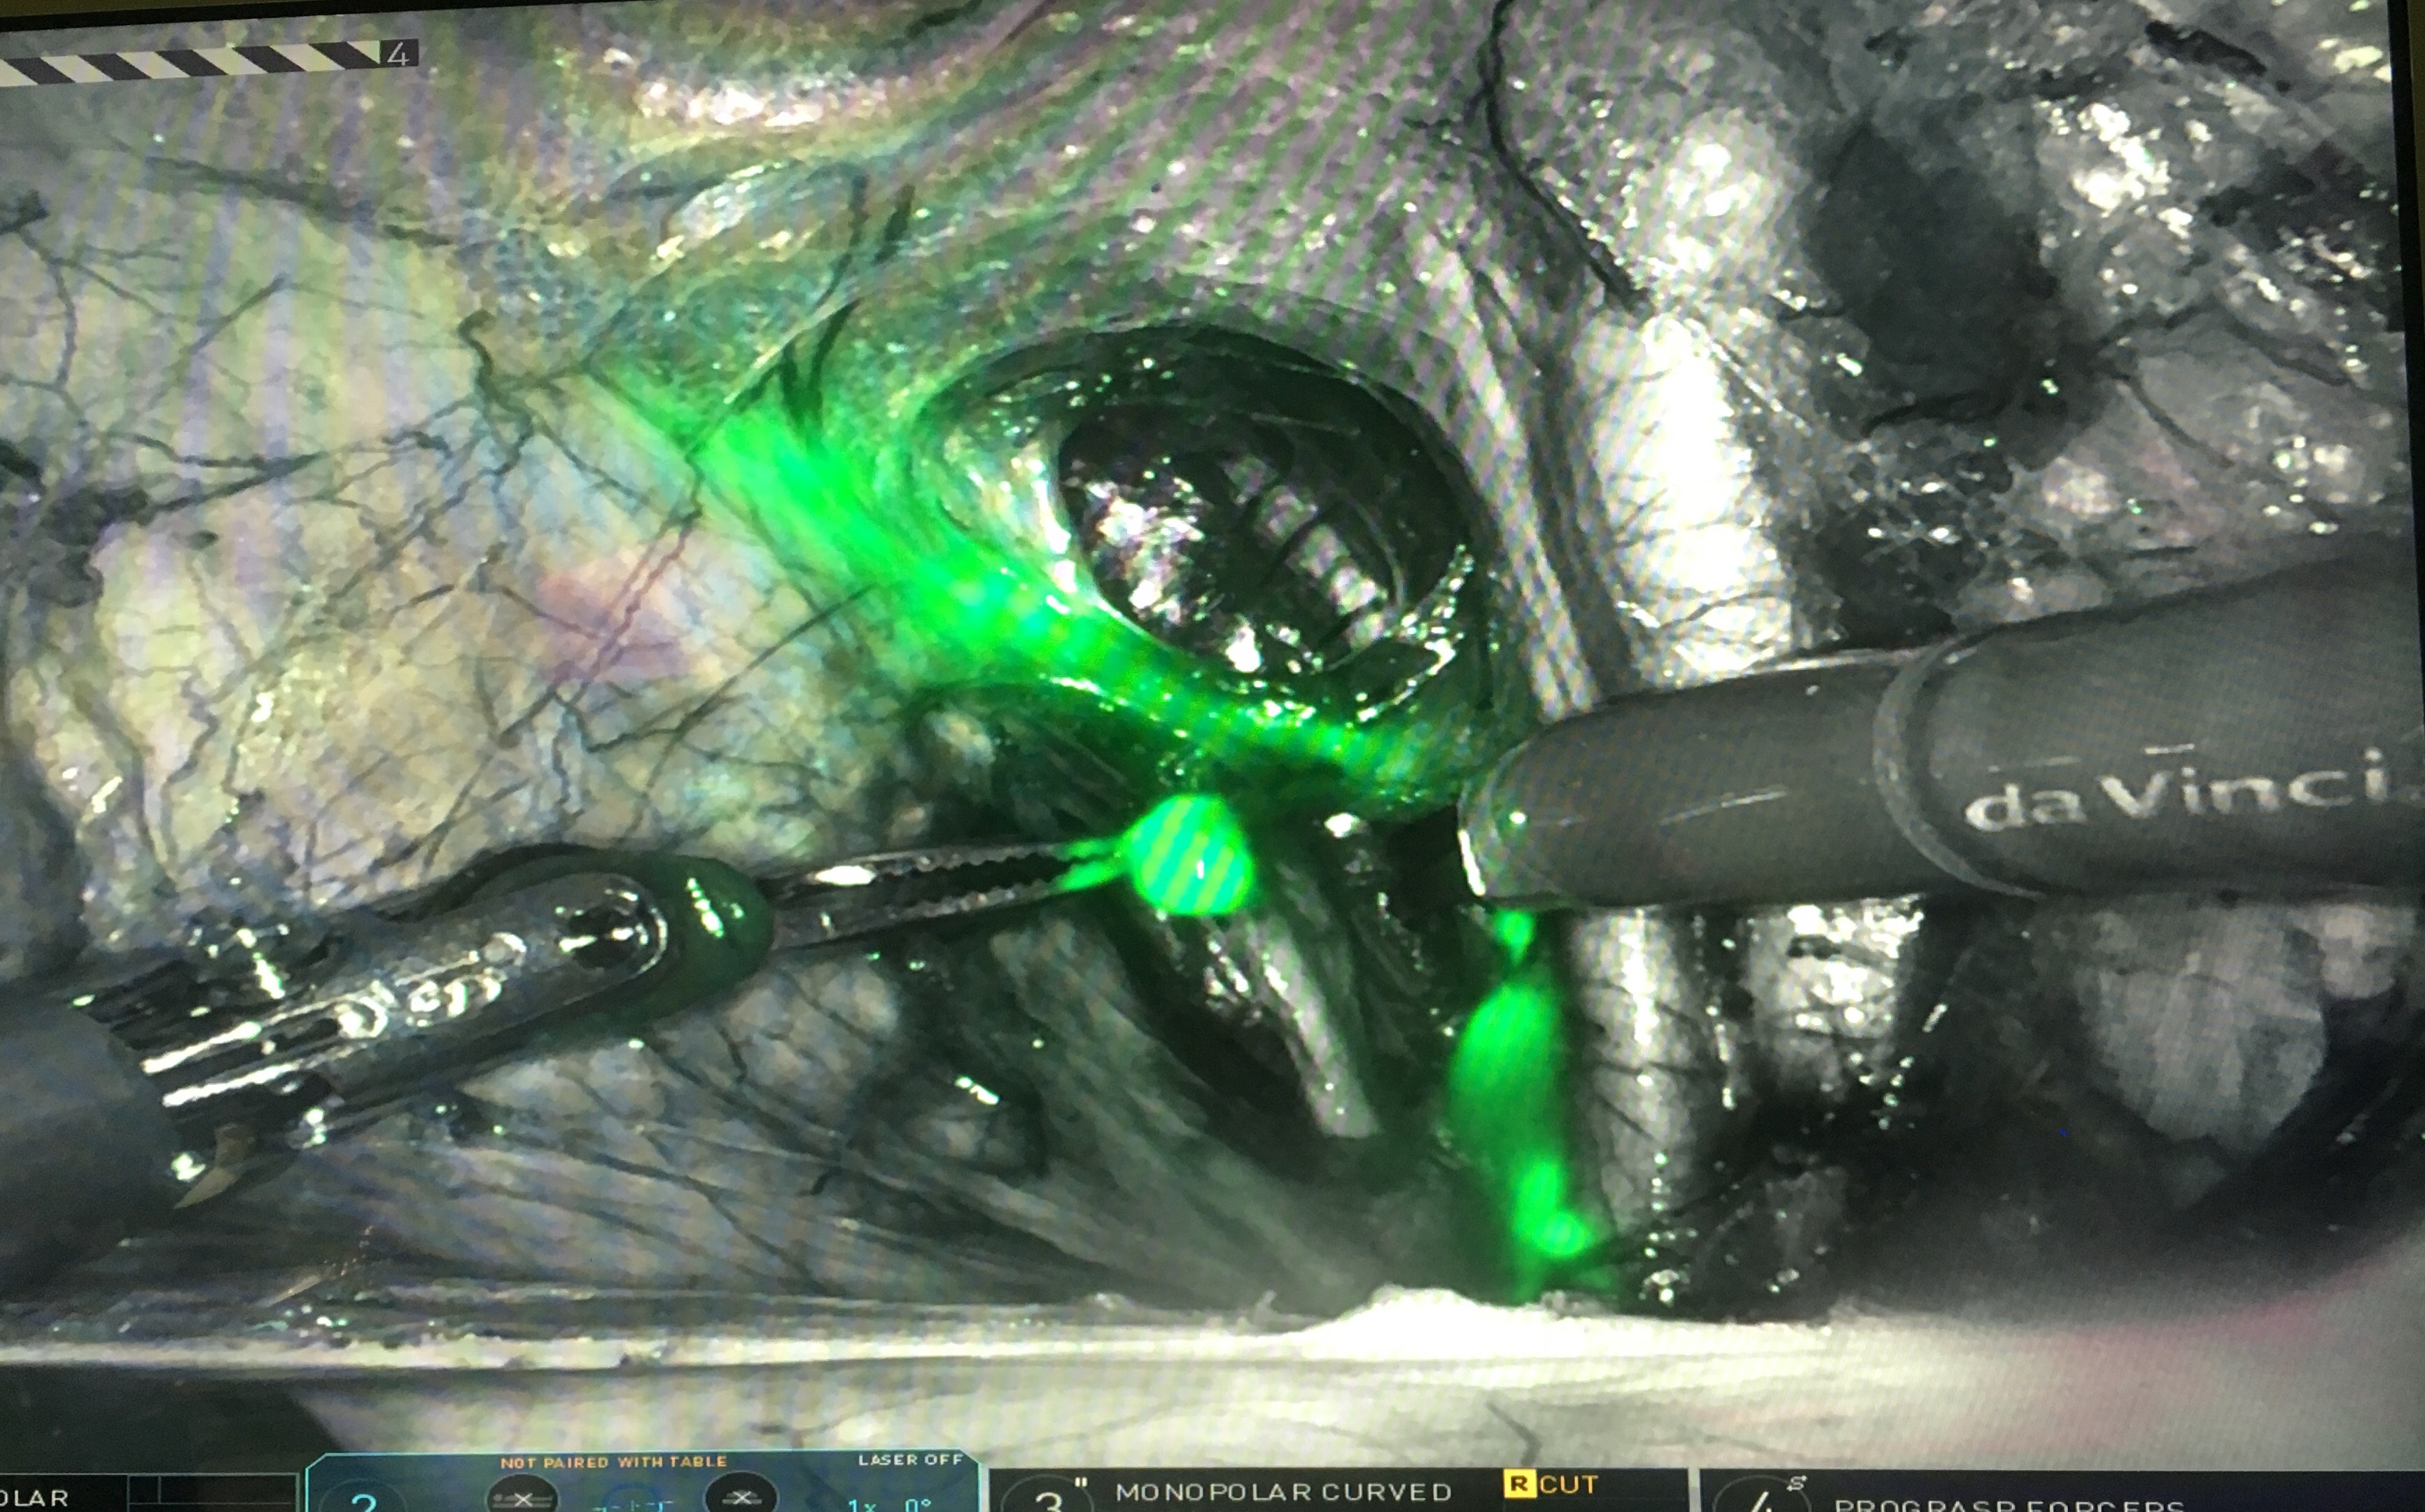

green dye2

Read more about "green dye2"... -